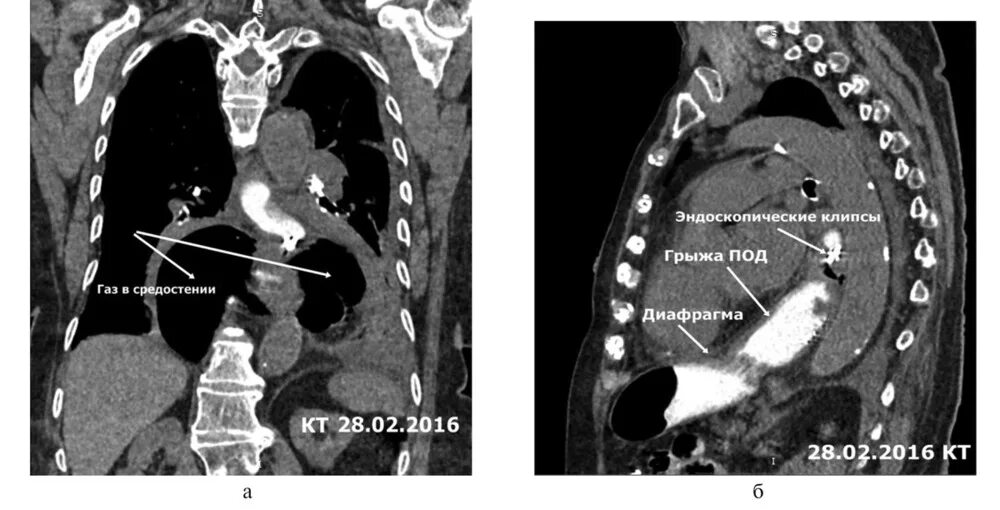

Грыжи на кт